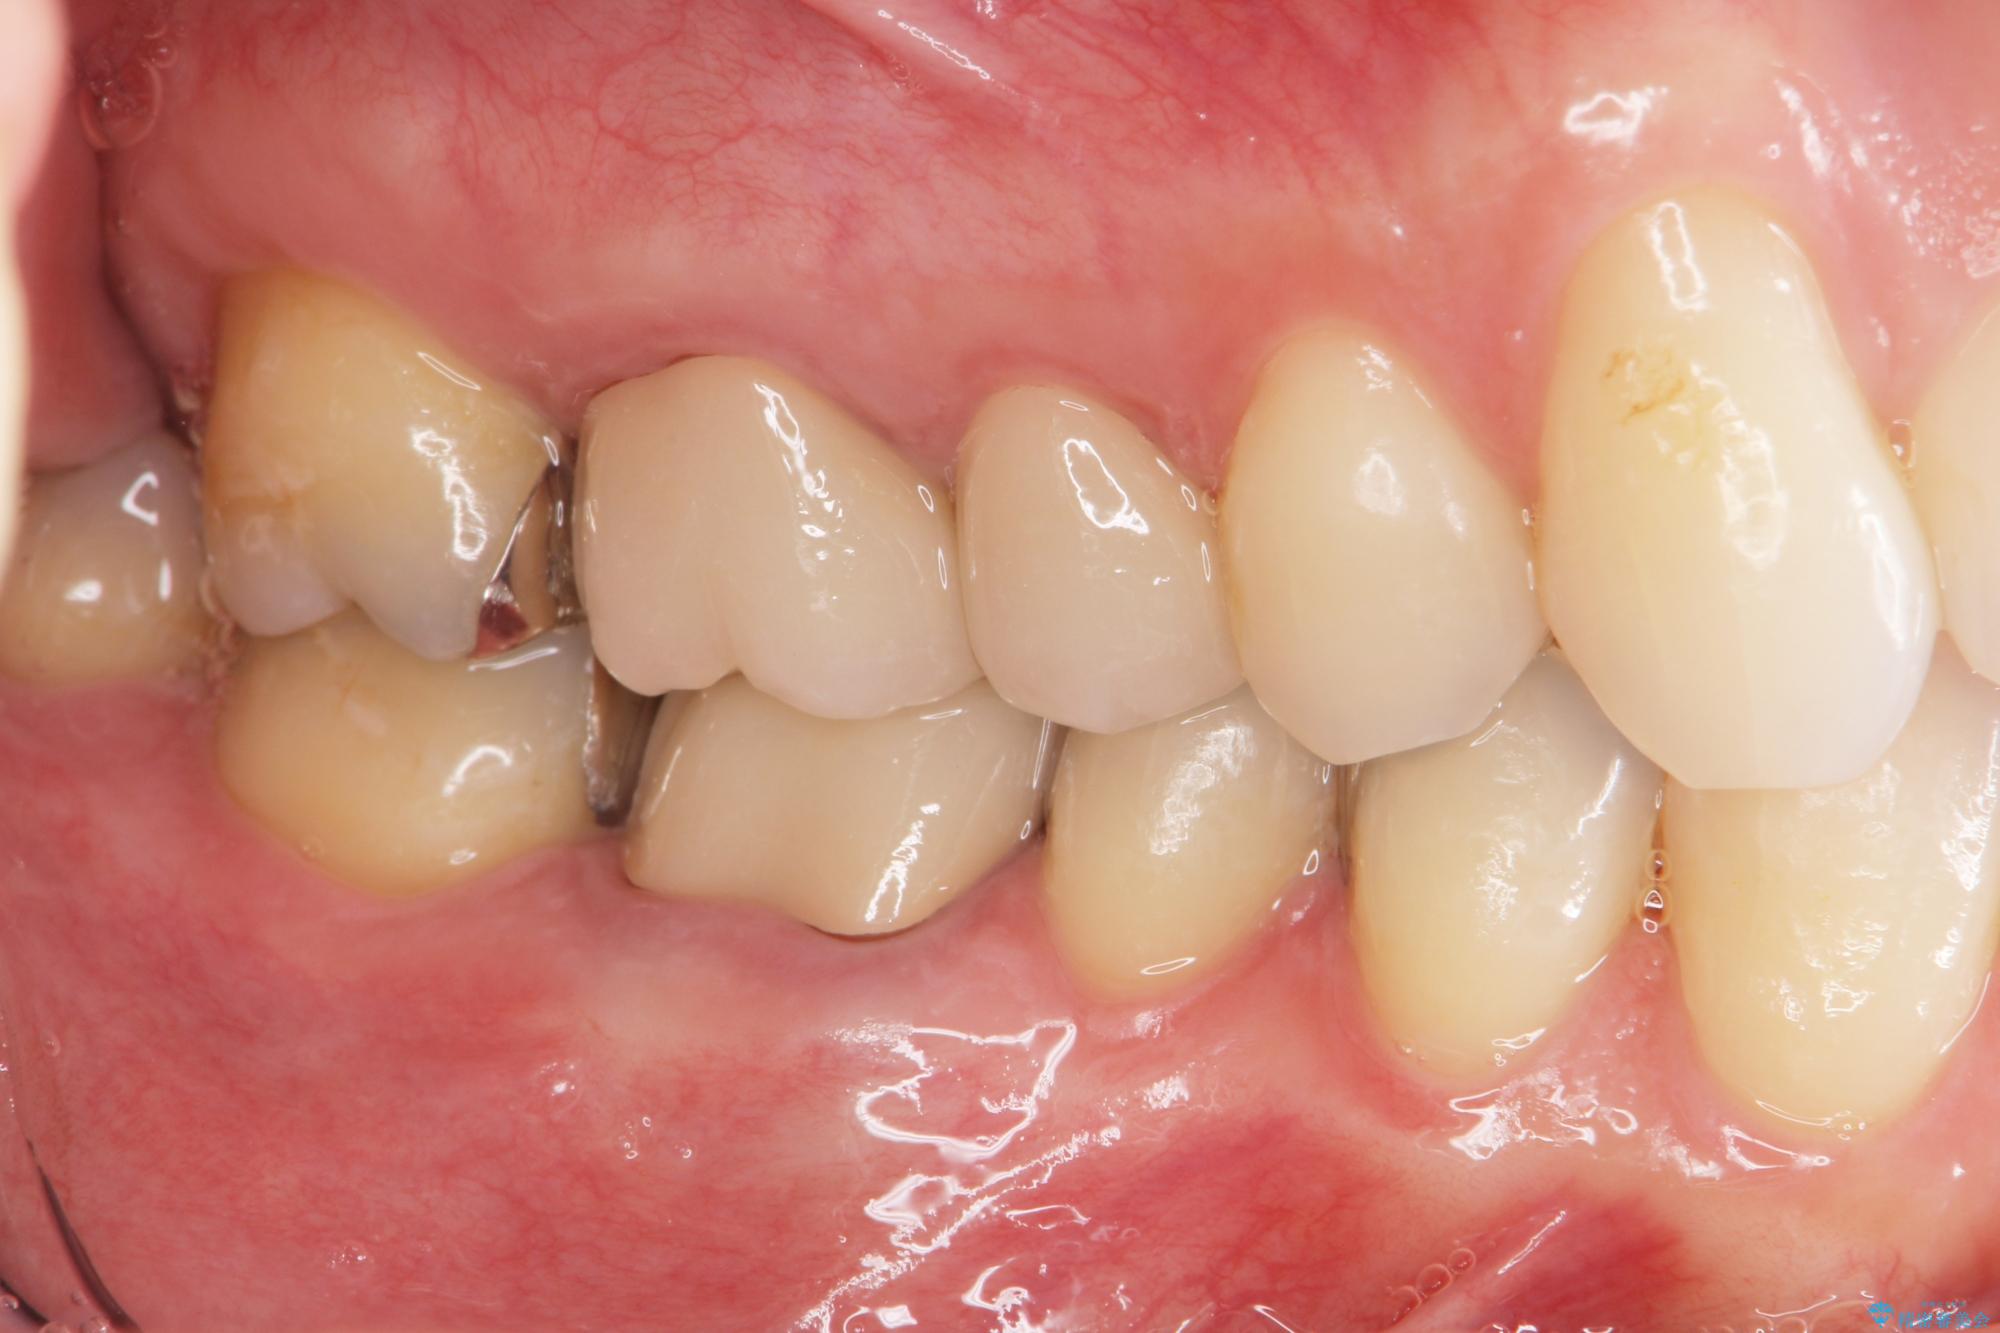

- 突き出た前歯の角度の改善と虫歯治療の改善を求めて来院されました。

虫歯を除去したのち、マウスピース矯正治療を行い、歯並びやがたつきを改善したのち、セラミックに置き換えることで審美性の向上を計画します。

矯正や虫歯治療、セラミック治療といった複合的な治療を一医院で行うことができるのが当法人の大きな特長です。